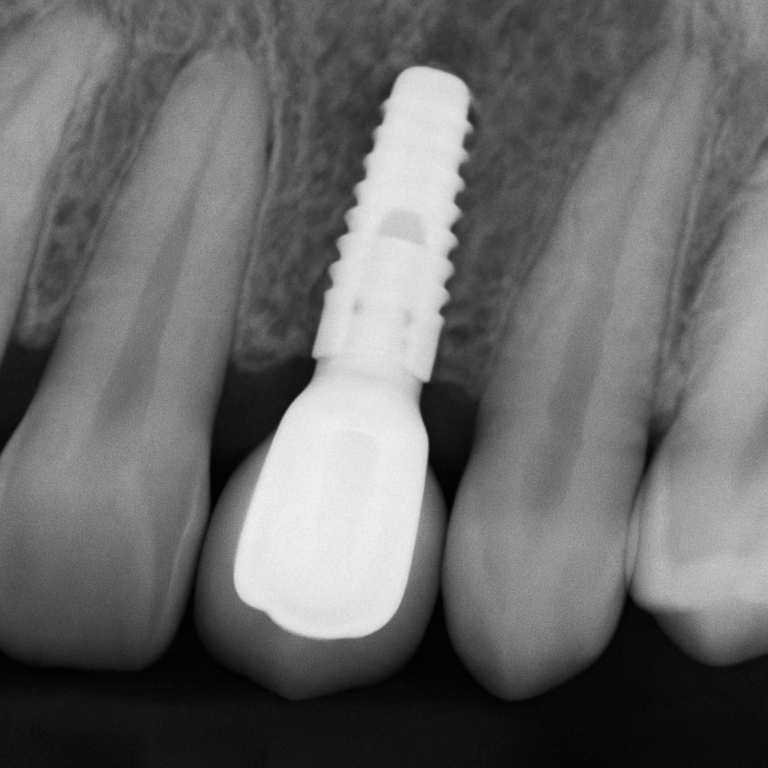

Curious about what is a tooth implant procedure? At its core, a tooth implant involves placing a titanium post into the jawbone, acting as a

Dental implants have revolutionized restorative dentistry, offering a durable solution for missing teeth. The concept of a complete dental implant goes beyond the basic idea

Dental implants have revolutionized the way individuals approach tooth restoration, offering a reliable and effective solution for missing teeth. These implants are small titanium posts